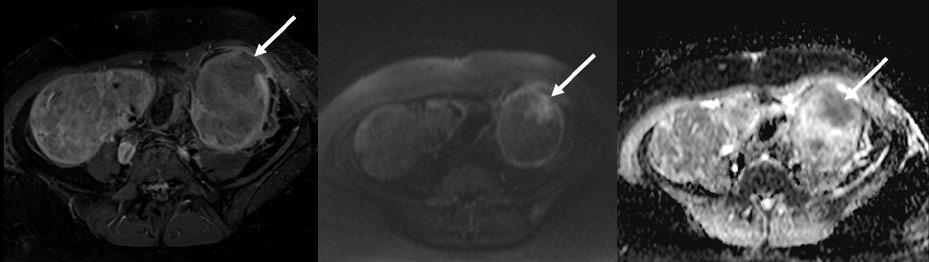

97 Challenges in Diagnosing Radiographic Axial Spondyloarthritis: A Case Study of a Young Adult in a Secondary-Level General Hospital in Guayaquil, Ecuador

Acuria et al.